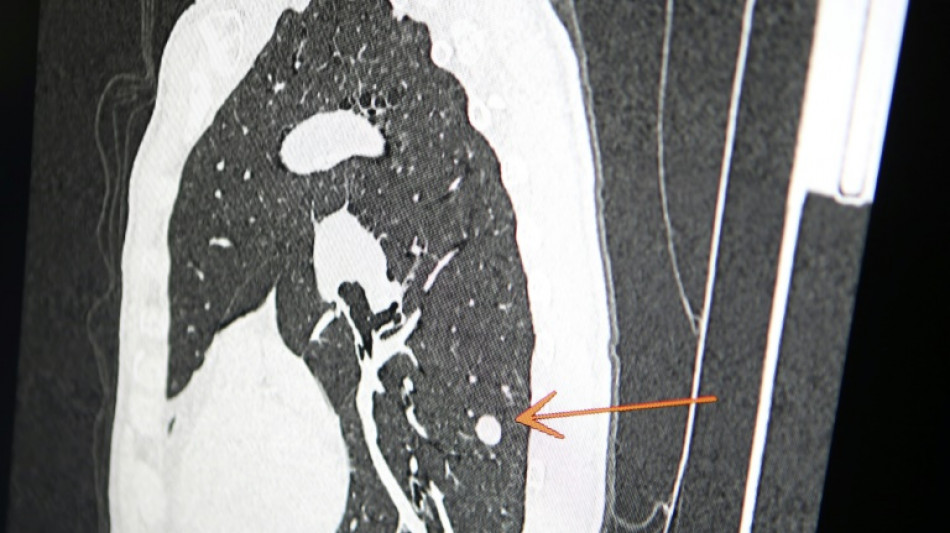

"Usted tiene cáncer", mensaje erróneo y aterrador a cientos de pacientes de una clínica en Inglaterra / Foto: Pascal Pochard-Casabianca - AFP/Archivos

Una clínica del norte de Inglaterra dio un gran susto a cientos de pacientes al enviar el mensaje "diagnóstico: cáncer de pulmón agresivo con metástasis" en lugar de sus buenos deseos de Navidad, informó el diario The Sun el jueves.

El 23 de diciembre a las 15H49, los pacientes de este centro de salud de Askern, cerca de la ciudad de Doncaster, recibieron un mensaje de texto en su teléfono informándoles de este diagnóstico, pidiéndoles que rellenaran los formularios correspondientes y concluyendo: "Gracias".